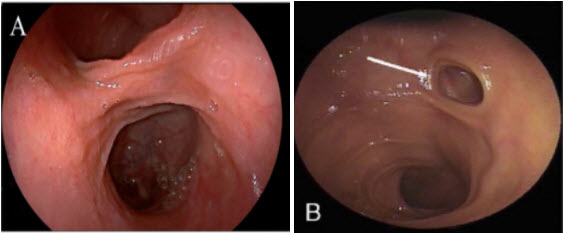

Nội soi bóng đôi(double-balloon enteroscopy): là một thủ thuật nội soi tiên tiến có thể khảo sát toàn bộ ruột non. Nó có thể thực hiện ngược dòng hay xuôi dòng. Chỉ định chính của nó là để chẩn đoán và điều trị các tổn thương chảy máu của ruột giữa trong đó có mục tiêu khảo sát nguyên nhân chảy máu có phải từ túi thừa meckel hay không?Trong nội soi bóng đôi túi thừa meckel có hình ảnh lòng ống đôi (Double lumen)(Hình 3). Hiện tạiBệnh viện của chúng tôi chưa có phương tiện này.

2021 09 08 14 12 01

Hình 3. Hình ảnh lòng ống đôi

A* Nguồn: theo Yang J (2020) [12]B* Nguồn: theo Chen Y. (2019) [1]